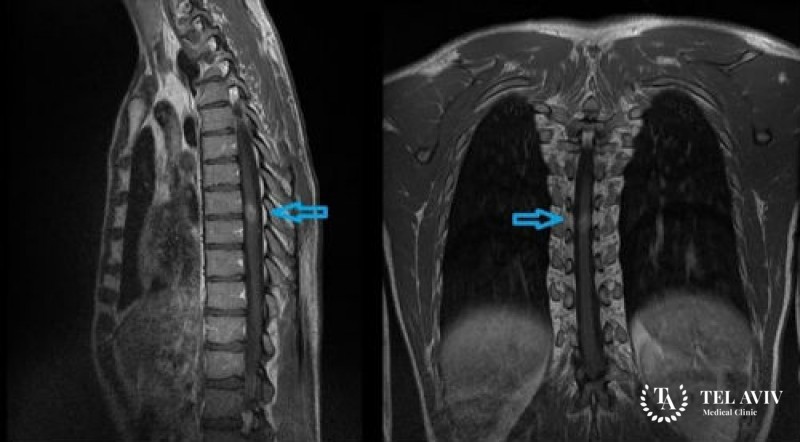

При любых подозрениях на наличие опухоли нужно сразу обращаться за медицинской помощью. После предварительного осмотра и опроса пациента врачом назначается компьютерная томография и магнитно-резонансная томография. Для определения характера новообразования проводится стереотаксическая биопсия, позволяющая получить фрагмент измененных тканей и провести их гистологическое исследование.